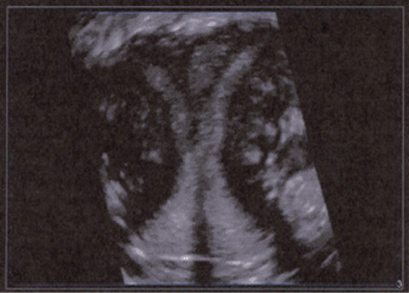

FIGURE 8–17. Multiplanar image of normal fetal spine. (Courtesy of Philips Healthcare.)

FIGURE 8–18. Multiplanar image of normal sacrum of a fetus at 26-weeks’ gestation. (Courtesy of Philips Healthcare.)